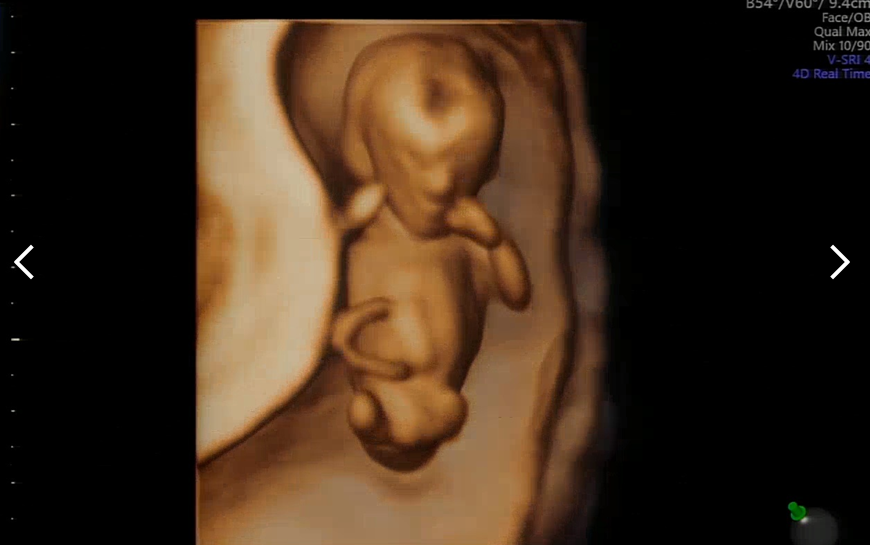

마지막으로 찍어주신 입체 초음파. 아직은 뭔가 외계 생명체같기도 하고 예쁘게 나오기 힘든 입체 초음파. 여러 컷 찍어주셨는데 얼굴을 가린 사진이 대부분이었다. 지금쯤 찍어야 태아 전신 샷을 입체로 남길 수 있다고 하셨다.